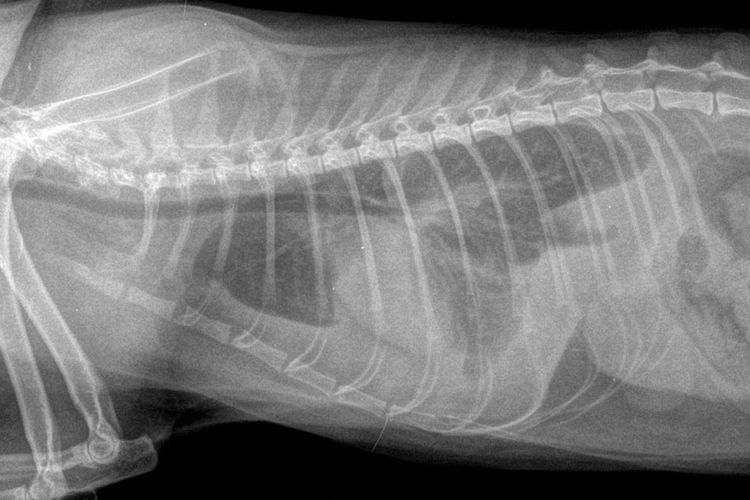

L'échographie est une méthode diagnostique informative qui permet de détecter une occlusion intestinale dynamique, la présence de corps étrangers dans le tube digestif et des modifications de la structure de la paroi intestinale. Dans certains cas, afin d'améliorer la précision de cet examen, une radiographie abdominale est réalisée chez le chat.